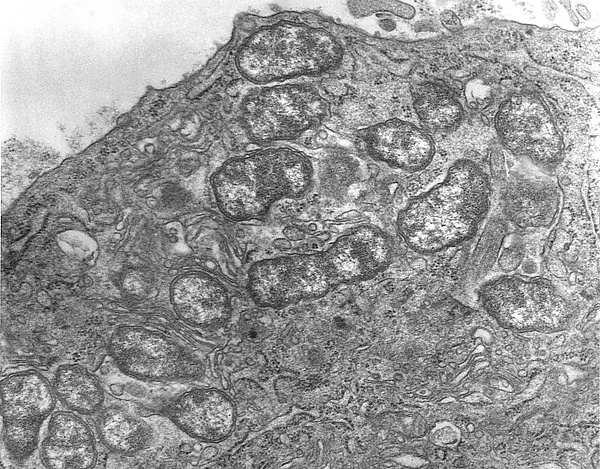

Возбудитель — Orientia tsutsugamushi (ранее R. tsutsugamushi, R. orientalis). Возбудитель обладает теми же свойствами, что и другие риккетсии. Антигенная структура O. tsutsugamushi позволяет выделить ряд сероваров: Gilliam, Karp, Kato, Fan. Все штаммы различаются по вирулентности и по антигенным свойствам. Есть штаммы, убивающие 80—100 % подопытных белых мышей, и штаммы, которые обусловливают у них только легкие клинические проявления. Риккетсии нестойки во внешней среде, моментально погибают при кипячении. Выделенные в нашей стране штаммы O. tsutsugamushi относятся к серовару Gilliam[7][8].

Патоморфология

В лимфатических узлах обнаруживают воспалительные изменения, развивается генерализованный лимфаденит. Гистологически — гиперплазия в фолликулах, откладывания фибрина, гиалиноз стенок сосудов, у части больных — коагуляционный некроз клеток. Почти у половины умерших от этой болезни обнаруживают очаговую или диффузную интерстициальную пневмонию.